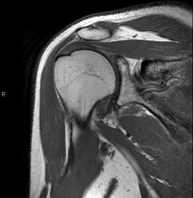

- RM Hombro

Exploración para el estudio de lesiones en tendones, músculos y articulación. Su principal utilidad reside en diagnosticar las lesiones de los tendones del manguito rotador. Tiene una duración aproximada de 20 minutos. No emplea radiación ionizante. - RM Brazo

Exploración para el estudio de lesiones en tendones músculos y pequeñas articulaciones. Permite valorar con eficacia las lesiones en el cartílago. También es de mucha utilidad para completar la exploración ecográfica previa. No emplea radiación ionizante. Tiene una duración aproximada de 20 minutos. - Artro-RM Hombro

Exploración para el estudio de las lesiones en pequeñas estructuras anatómicas de la articulación que suelen lesionarse en pacientes que sufren luxación o inestabilidad crónica. El estudio viene precedido por una inyección de contraste en el interior de la articulación, realizada bajo control de rayos X. La duración global de los dos procedimientos es de 50 minutos. - Artro-RM Muñeca